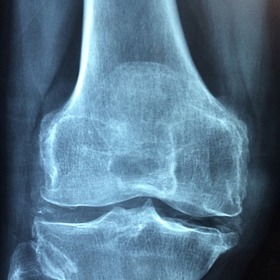

Nemoc přichází pomalu a většina pacientů si prvotních příznaků ani nevšimne. Proto si vysloužila přezdívku „tichý zloděj“ - člověka obírá o kosterní hmotu tak dlouho, dokud na problém neupozorní první zlomenina. V tu chvíli už stačí jen minimální náraz nebo upadnutí. Nejvíc náchylné k frakturám bez zjevných příčin bývají obratle, krčky stehenních kostí nebo předloktí.

Mnoho lidí své problémy mylně pokládá za přirozený projev stárnutí. Zakulacující se záda, snížení výšky postavy i o tři centimetry, bolesti páteře a dlouhých kostí nebo potíže při hlubokém nádechu do břicha nepovažují za podstatné a přehlížejí je. Včasná diagnostika přitom výrazně napomáhá zpomalit nebo zastavit progres nemoci.